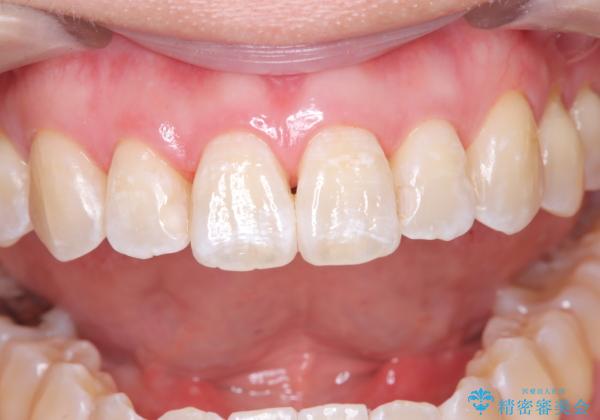

- 治療計画

- 定期的にメンテナンスで来院されている方から歯を白くしたいと相談され、自然な色味希望と歯の表面のべたつき感じからエアーフローとホワイトニングをご提案しました

歯の表面に多少の白濁はでていますが、色味のトーンが上がったため満足して頂きました